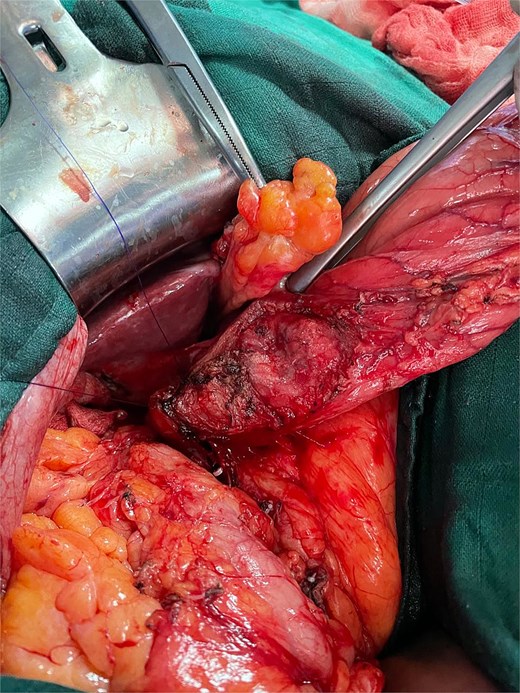

Surgical exploration revealed the true pathology: acute complicated cholecystitis with gallbladder fistulization to the subserosal gastric wall in the antro-pyloric region (Fig. 3), without mucosal involvement. The apparent ‘second gallbladder’ on imaging was actually a pseudocystic formation created by the fistulous communication and inflammatory process. The area was surrounded by significant inflammatory adhesions involving the omentum, creating a complex inflammatory mass.

Intraoperative view showing cholecystitis of a sclerotic and atrophic gallbladder associated with a cholecysto-gastric fistula.